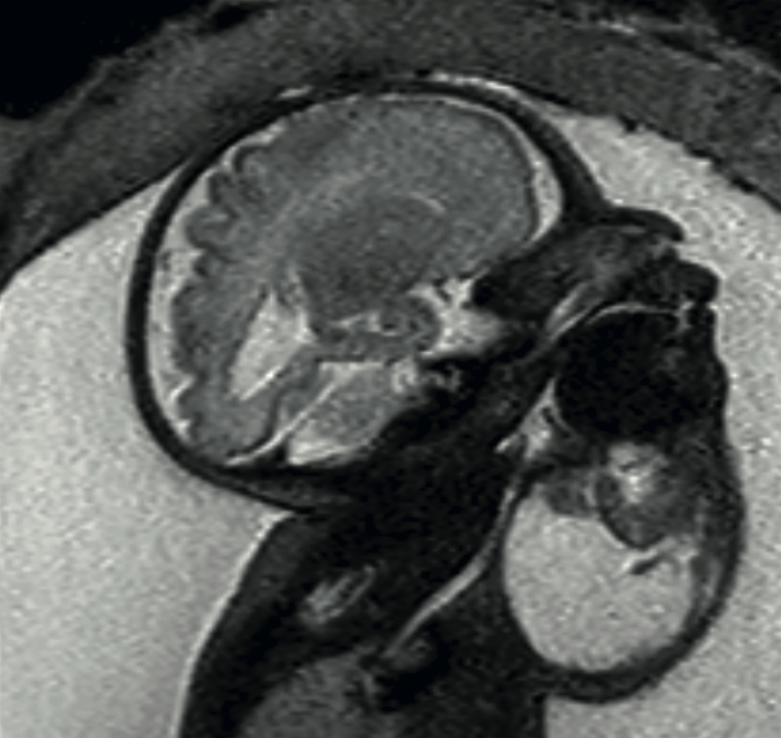

<strong>Figura 1</strong>

Figura 1. Resonancia a las 32 semanas, secuencia T2, feto con hiperextensión del cuello, secundaria a lesión quística, con escaso componente sólido en el hemicuello derecho.